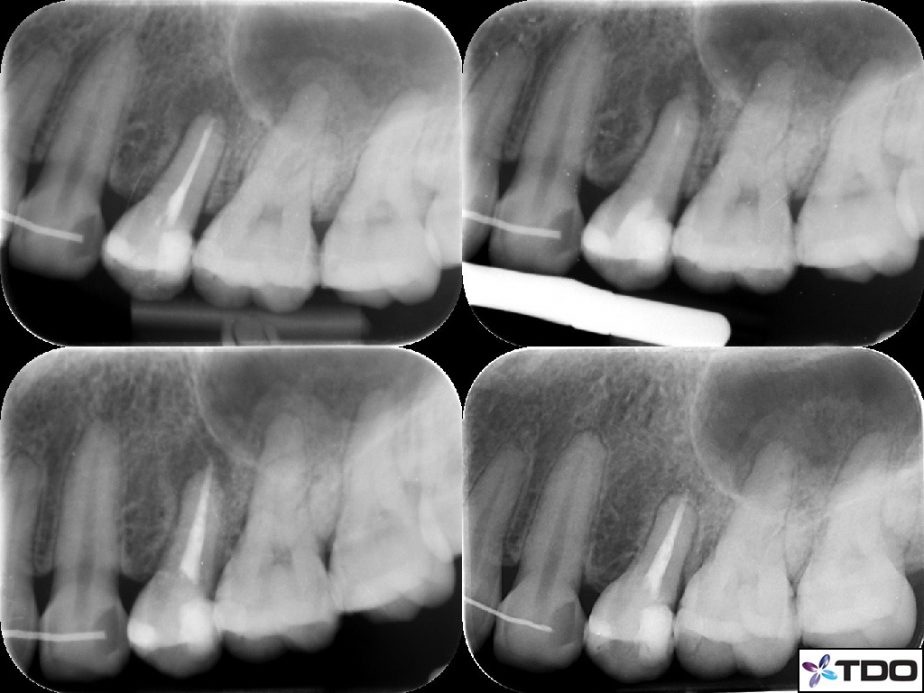

Patient D presented with a dental abscess associated with tooth 25. The tooth had been previously endodontically treated with an Endodontist in the patient’s teens and had developed issues, eight years later. Orthograde endodontic retreatment was performed for the tooth over two visits with calcium hydroxide dressing.

At the first visit, the tooth was accessed and old gutta-percha remnants removed using retreatment files D1, D2, D3. The shaping of the canals was achieved with ProTaper Next instrumentation X2. The canal was purposely over instrumented with a small no. 10 k-file to ensure patency, and calcium hydroxide was placed.

Three weeks after debridement was completed Patient D was asymptomatic, and the dental abscess had resolved. The tooth was obturated with gutta-percha and AH Plus sealer.

The endodontic review at 6 months, showed evidence of increased bone deposition in the periapical area. Patient D was relieved as she had no issues with the tooth following treatment.